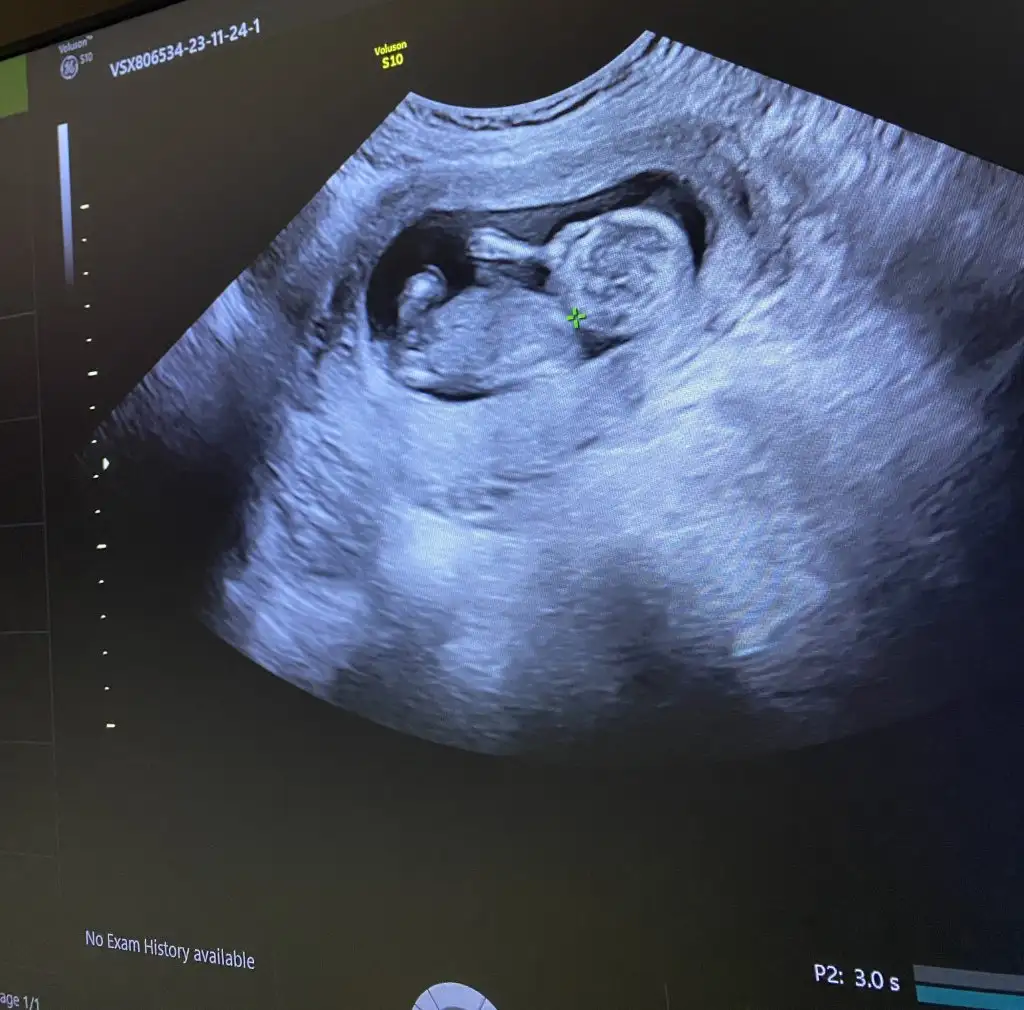

9 haftalıktan 12 haftalığa kadar koydum canım bende çok merak ediyorum cevabını bekliyorumSelam Kızlarbir çok kişi gruplardan beni bilir. Yine yetiştim imdatlara

5 ve 14. haftaya kadar olan ultrason fotolarınızı paylaşın. Vajinadan mı yoksa karından mı çekildiğini ve kaç haftalık olduğunu da mutlaka belirtin.